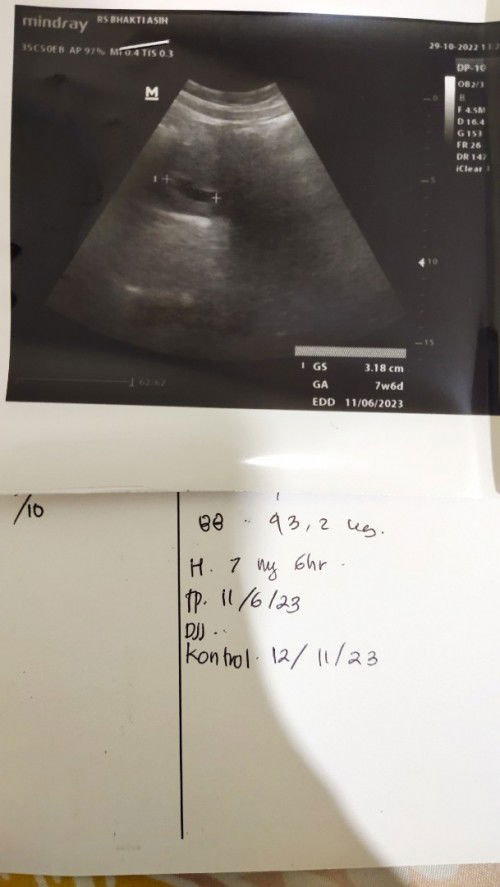

seminggu kemarin sakit demam, pusing, dan lebih parah ada lambung, sempet ke puskesmas dikasih obat antasida dan paracetamol. di hari sabtu jadwal kontrol per2 minggu sekali, dari awal sakit pikiran udah ga karuan takut kenapa" sama janin karna makan gamau, selalu mual", apalagi makan nasi ga bisa sama sekali. pas di cek ada kelemahan di kehamilanku, dia berkembang sekarang usianya 8 minggu tapi takut ga berkembang. Tapi dokter masih bilang normal karna aku ga ada keluar flek. betapa sakitnya aku, aku terus minta maaf ke calon anakku, aku terus berusaha untuk jaga calon anakku ini. kata dokter aku disuruh banyak makan karna mungkin itu pemicu janin yang katanya "agak gepeng". maaf guys cuma mau cerita rasa sakit ini 🙏